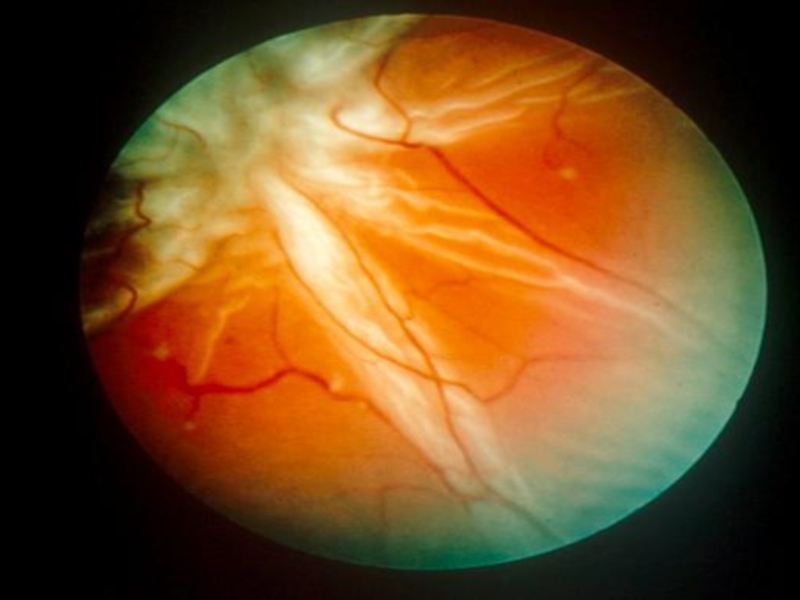

Слайд 7Свежая отслойка сетчатки

Свежая отслойка сетчатки